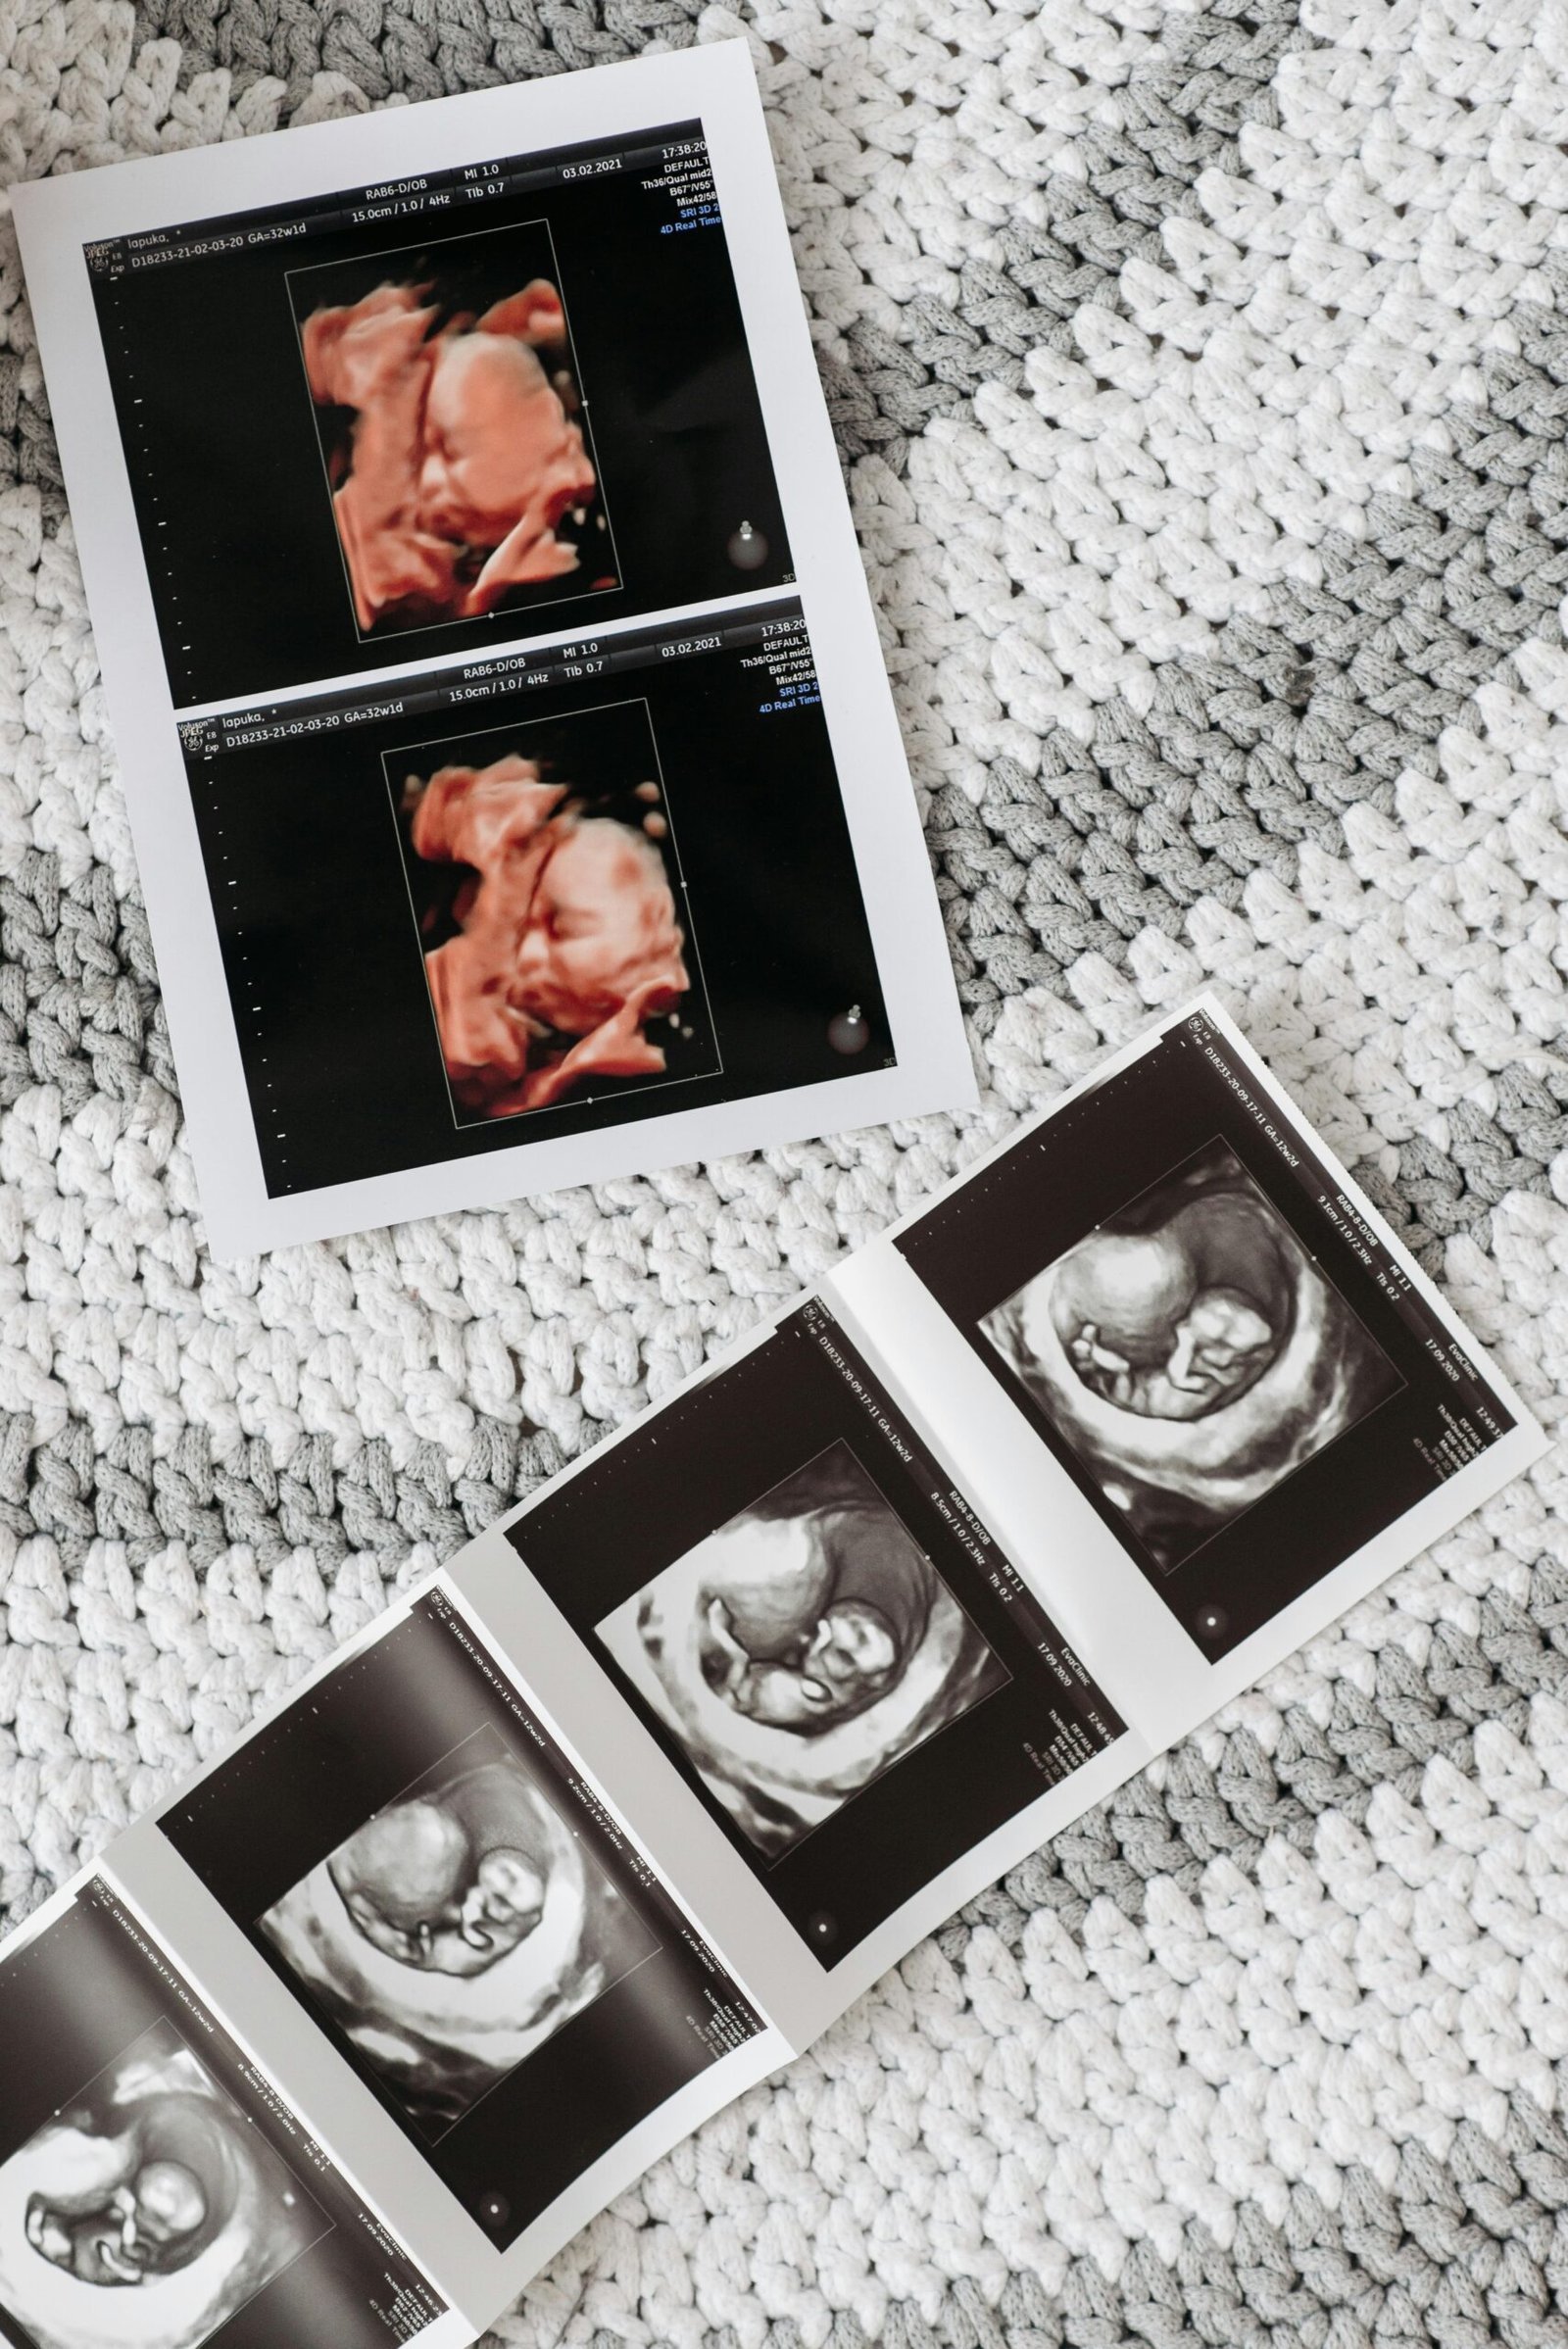

Ultra Sonido Obstetrico.

Ofrecemos ultrasonidos obstétricos de alta precisión para monitorizar el desarrollo de tu bebé. Nuestro equipo capacitado utiliza tecnología avanzada para garantizar diagnósticos precisos y un seguimiento personalizado. Esto asegura un ambiente seguro y confiable para las mamás durante todo el embarazo.